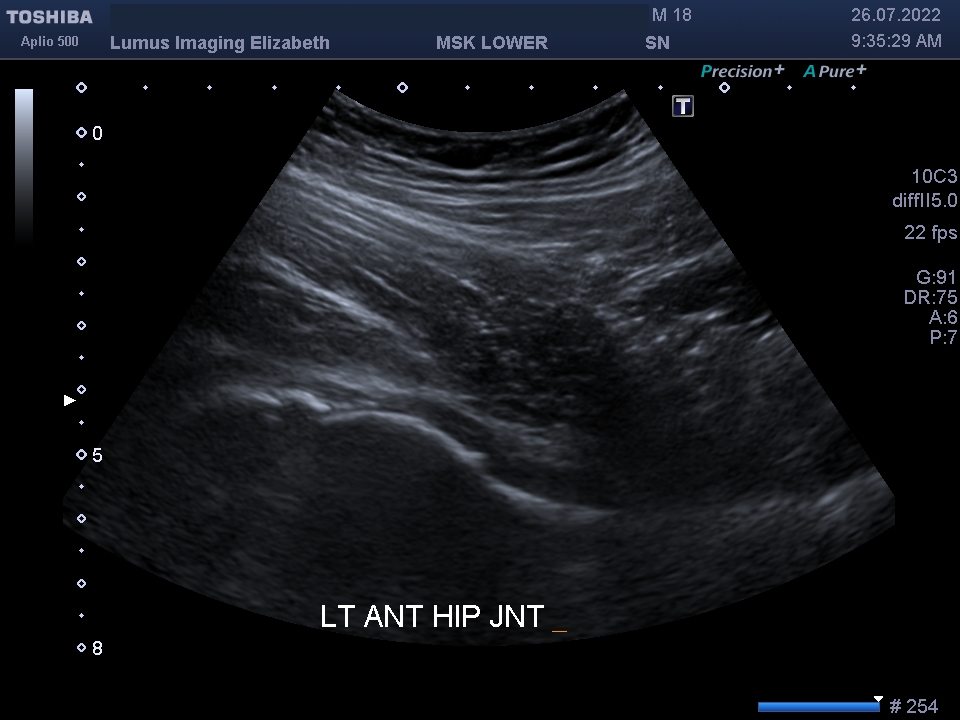

I202207261120112060009

Son Nguyen

26/07/2022